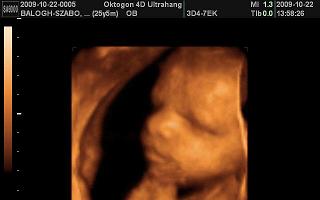

Voltam 4D-n nagyon szuper volt, csak nekem is ugyanaz volt a gond, hogy szinte végig hátat fordított. Az utolsó 10 percben lehetett egy kicsit látható pózban elkapni egy pár fotót róla. De így is megérte mert annyira jó volt látni a kicsi arcát. :D :D

Kép 28+3 naposan a kicsi Lili